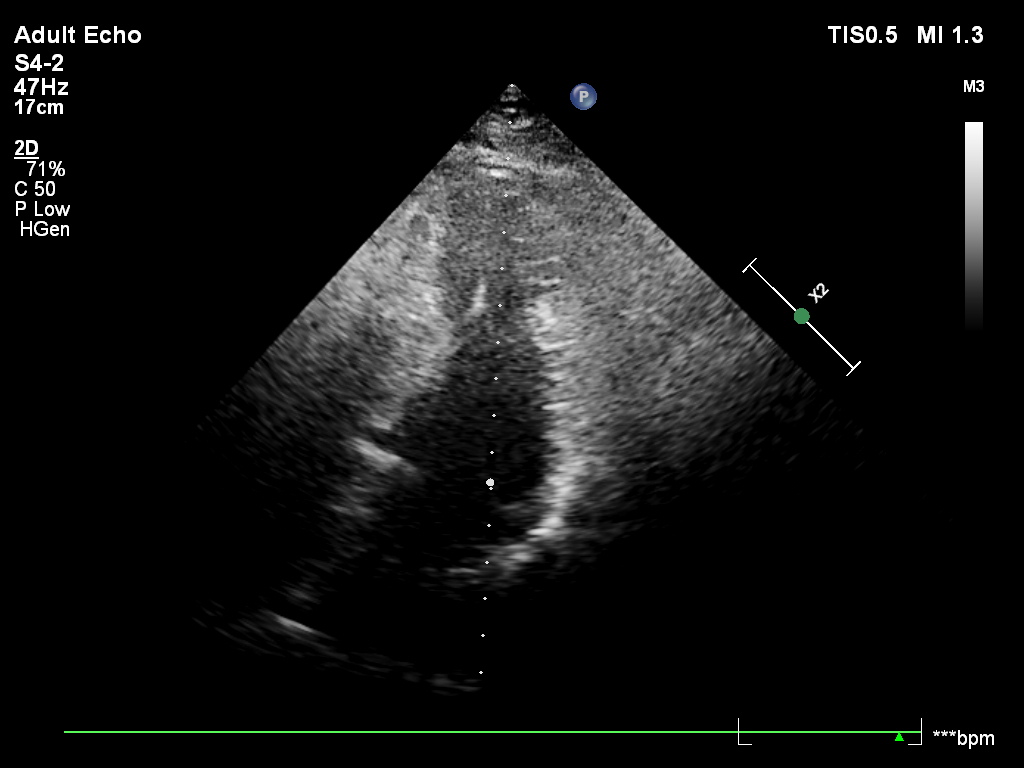

Pacjent , lat 66, przyjęty z podejrzeniem sepsy, w badaniu echokardiograficznym ujawniono duże, ruchome wegetacje na trzech zastawkach – mitralnej, trójdzielnej i płucnej . Wegetacje najlepiej widoczne były w projekcjach podmostkowych . Obraz jest dramatyczny: wysokie ryzyko powikłań zatorowych i przeciążenia prawego serca.

A 66-year-old patient admitted with suspected sepsis underwent echocardiography, revealing large, mobile vegetations on the mitral ,tricuspid and pulmonary valves .Vegetations were most clearly visualized in subcostal projections. The findings are dramatic, indicating a high risk of embolic complications and right heart overload.

w projekcji – podmostkowej 4 jamowej uwidoczniono wegetacje na zastawce trójdzielnej i mitralnej

wegetacja na płatku przednim zastawki mitralnej (segment A2) projekcja podmostkowa poprzeczna na zastawkę mitralną